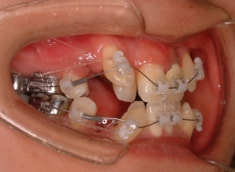

治療開始から約1年後

骨格的な下顎前突の傾向は強くはありませんが、歯牙の状態によって反対咬合が認められます。LowTongue(低位舌)もあります。